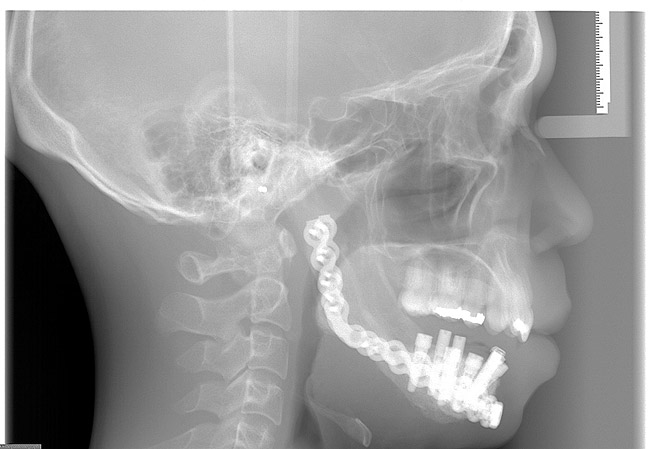

Prior to implant placement, the vertical dimension of occlusion had to be reestablished and a new functional posterior occlusal plane developed. Within this framework, the axial position of the implants could be established. However, the positions of these implants were not solely predetermined by the bony architecture of the newly reconstructed mandible but also could be altered to conform to the proportional harmony of the lower face. To assist in this determination, a left lateral skull film was obtained (Figure 7) and an analysis of facial form, vertical dimension, and incisor position was performed. It was determined that the vertical dimension of the lower face would need to be increased; the posterior occlusal plane would need to be intruded; and the axial position of the lower incisor implants would have to be upright over the newly augmented ridge. In order to establish an esthetic anterior occlusal plane, the upper incisors would have to be retracted without extrusion.9 Final vertical dimension was confirmed by a CBCT scan with a modified surgical guide in place (Figure 8), and this same guide was used for the placement of 10 endosseous dental implants. Then, a transitional lower denture was fabricated and orthodontic treatment was instituted while the implants were allowed to integrate.

Figure 7  Cephalometric x-ray with an analysis of facial form, vertical dimension, and incisor position.

Figure 7